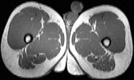

Visible Human male: Sectio transversalis 1992

CT

NMR

Pd                          / T2 \                         T1